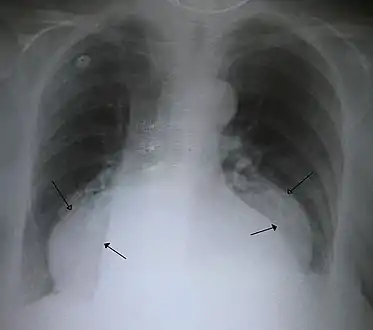

Diagnosis

The diagnosis of a hiatal hernia is typically made through an upper GI series, endoscopy, high resolution manometry, esophageal pH monitoring, and computed tomography (CT). Barium swallow as in upper GI series allows the size, location, stricture, stenosis of oesophagus to be seen. Besides, it can also evaluate the oesophageal movements. Endoscopy can analyse the esophageal internal surface for erosions, ulcers, and tumours. Meanwhile, manometry can determine the integrity of esophageal movements, and the presence of esophageal achalasia. pH testings allows the quantitative analysis of acid reflux episodes. CT scan is useful in diagnosing complications of hiatal hernia such as gastric volvulus, perforation, pneumoperitoneum, and pneumomediastinum.[8]